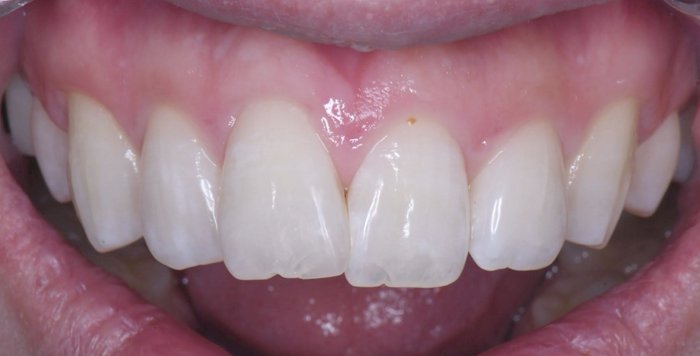

症例2:欠けた歯を治したい

治療前

治療後

治療中の様子

修復した最後に、酸素で阻害された表面(Oxygen Inhibitation Layer)を最終重合しています。

| 主訴 | 欠けた歯を治したい |

|---|---|

| 治療期間 | 1日 |

| 治療費 | ¥22,000 |

| 治療内容 | コンポジットレジンにて修復しました。切端の透明感や亀裂(クラック)を隣の歯と同じように再現できました。患者様には大変満足していただけました。 |

| 治療のリスク | 欠けたり、経年的な変色の可能性があります。 |